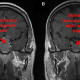

Pasien dengan kasus tumor Pituitary Fungsional dengan ukuran makro, tanpa disertai defisit neurologis fokal, diterapi dengan terapi Bromocriptin. Apakah kemungkinan tumor akan mengecil? Jika tidak ada defisit neurologis kapan perlu evaluasi pasien tersebut ?

Evaluasi ulang MRI biasa dilakukan sesuai prosedur center masing-masing secara berkala, biasanya 3 bulan, 6 bulan, atau 1 tahun setelah terapi dilakukan.